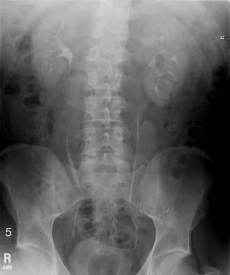

An intravenous pyelogram (IVP) is an x-ray examination of the kidneys, ureters and urinary bladder that uses iodinated contrast material injected into veins. The procedure is used to visualize abnormalities of the urinary system, including the kidneys, ureters, and bladder.

X-rays are taken at specific time intervals to capture the contrast as it travels through the different parts of the urinary system. This gives a comprehensive view of the patient’s anatomy and some information on the functioning of the renal system. Any obstruction in the system is visualized.